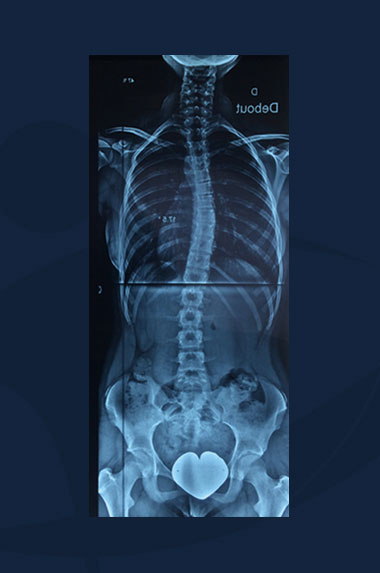

Jessica Specter

Clichés radiologiques du rachis (sans corset).

Scoliose Dorso-lombaire